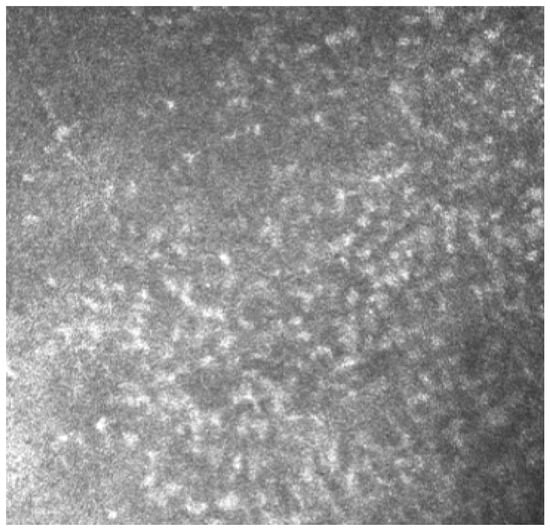

In Group 2, we observed that both eyelids showed mild-to-moderate distorted anatomy at Meibography. At the confocal examination, we observed a decrease in the goblet cell population in the conjunctival epithelium in this group (5.2 cells/mm); in some cases, goblet cells totally disappeared (Figure 5). In tarsal conjunctiva, inflammatory cells were present, and more concentrated around the adenoid lumina of the meibomian glands. We observed several cell infiltrates, composed of a mix of round cells and cells with multilobate nuclei compatible with neutrophils, which were probably a sign of an inflammatory process involving the conjunctiva (Figure 6).

In vivo confocal microscopy provides non-invasive high-resolution images of ocular surface tissues, bypassing the need for biopsy and/or impression cytology. Our in vivo images of bulbar and tarsal conjunctiva, acquired by confocal microscopy, confirmed the reduction in intraepithelial goblet cells as reported in the literature in patients treated with Dupilumab (Figure 5) [7]. Goblet cells are round cells, that occur mainly individually or in clusters, and normally account for 10% of the conjunctival epithelial cells [17]. We found a mean value of 5.2 cells/mm. In addition, the in vivo images show inflammatory cells in the tarsal conjunctiva and around the adenoid lumina. We assumed that the inflammation could be the cause behind the dropout of glands.

Figure 5. In vivo images of bulbar conjunctiva of a naive patient (left) and treated patient (right). Note the presence of intraepithelial goblet cells (arrow) on the left, while they are absent in the image on the right.